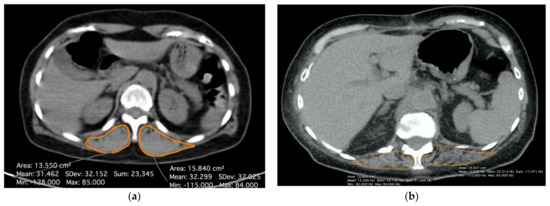

2.2. Radiological Evaluation of the Sarcopenia